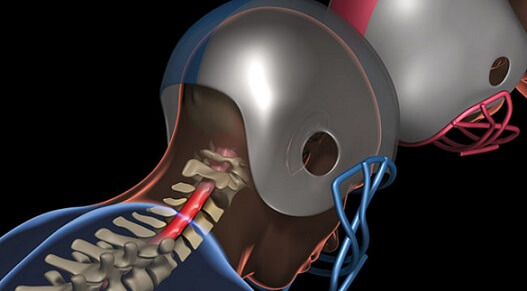

Lumbar Radicular Pain is Back or neck pain that travels into the leg or arms respectively considered as radicular pain, especially when it is radiating below the knee and elbow which leads to a condition called sciatica in leg and brachialgia in arms. Commonly the systems are associated with back pain with symptoms such as tingling and numbness sensations, weakness, stiffness and occasionally involvement of bowel and bladder sensation commonly known as “Cauda Equina Syndrome”. It is a serious problem in the spine & an emergency where the pinched nerve roots have to be freed immediately.

Spine surgery deals with any ailment which arises from the affliction of the spinal column, be it the vertebral bodies, the spinal cord or nerves, protruded intervertebral discs or joints.

Yes it is safe however there's few complications that will be related to style of surgery consequently which may be with any surgery, there's the danger of complications. Once surgery is done close to the spine and funiculus, these complications (if they occur)can be very serious. Please discuss the complications related to surgery with your doctor before surgery, Your doctor will best judge your condition and inform you of the risks involved.